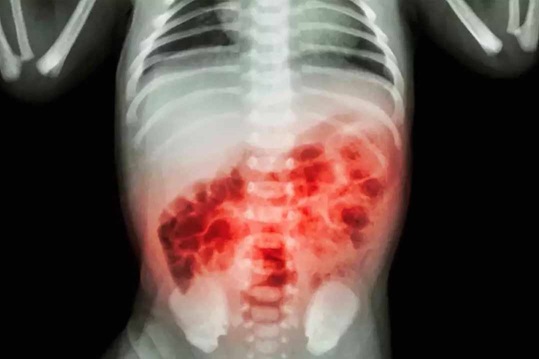

Viêm ruột hoại tử (NEC)

Ruột non xung huyết rộng, thành ruột phù nề là biểu hiện X-quang điển hình của bệnh NEC.

NEC là một trong những bệnh cấp cứu thường gặp ở trẻ sơ sinh với biểu hiện tổn thương hoại tử nghiêm trọng của ruột do sự tác động của đa yếu tố như mạch máu, cơ thành ruột, chuyển hóa và các yếu tố khác. Rối loạn đặc trưng bởi hoại tử thiếu máu cục bộ của niêm mạc ruột, dẫn đến các phản ứng viêm nặng nề, nhiễm trùng và sinh hơi, đưa khí vào thành ruột và hệ thống tĩnh mạch cửa. Theo thống kê, có 2 đến 10% trẻ sơ sinh < 1.500 g bị NEC làm tăng tỷ lệ tử vong hoặc ảnh hưởng tới quá trình phát triển tâm thần, vận động ở trẻ. Ngoài ra, 10% trẻ sinh non bị NEC sẽ gặp các vấn đề về đường tiêu hóa (đi tiêu phân lỏng kéo dài và nhiều lần), ảnh hưởng đến chất lượng sống.